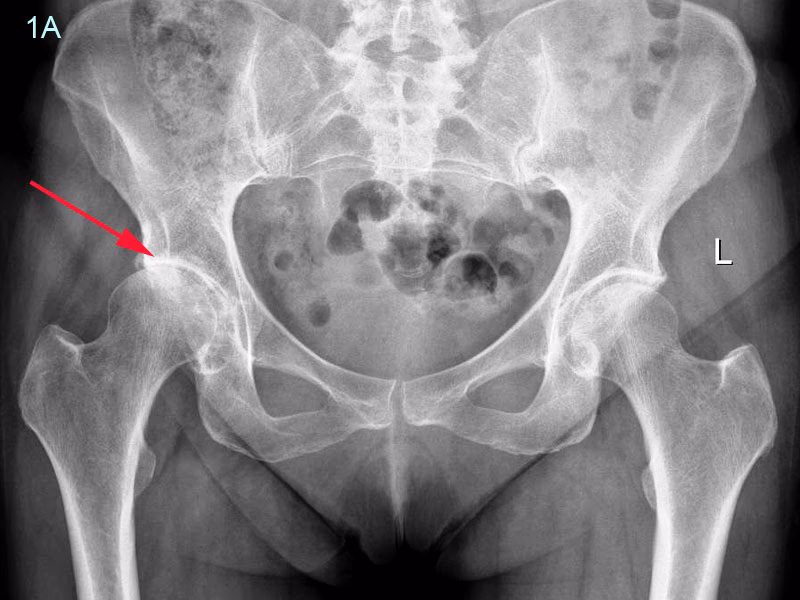

Processen med at nå frem til en af disse koder starter hos lægen. En grundig samtale om symptomer, sygehistorie og en fysisk undersøgelse er første skridt. Lægen vil vurdere din bevægelighed, stabilitet og lokalisere smertens præcise kilde. Ofte vil billeddiagnostik som røntgenbilleder være nødvendigt for at se tilstanden af brusk og knogler. I nogle tilfælde kan MR-scanninger eller blodprøver også komme på tale for at udelukke andre sygdomme.